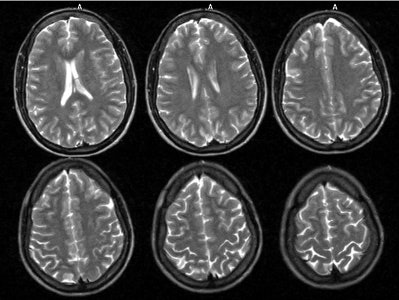

Neuro lyme: The patient below complained of intermittent right facial numbness, memory loss, and change in personality. Lyme titers were positive. MR imaging of the brain demonstrated no anatomic abnormality. SPECT imaging revealed multifocal areas of decreased perfusion in a pattern consistent with Lyme encephalopathy. |

|